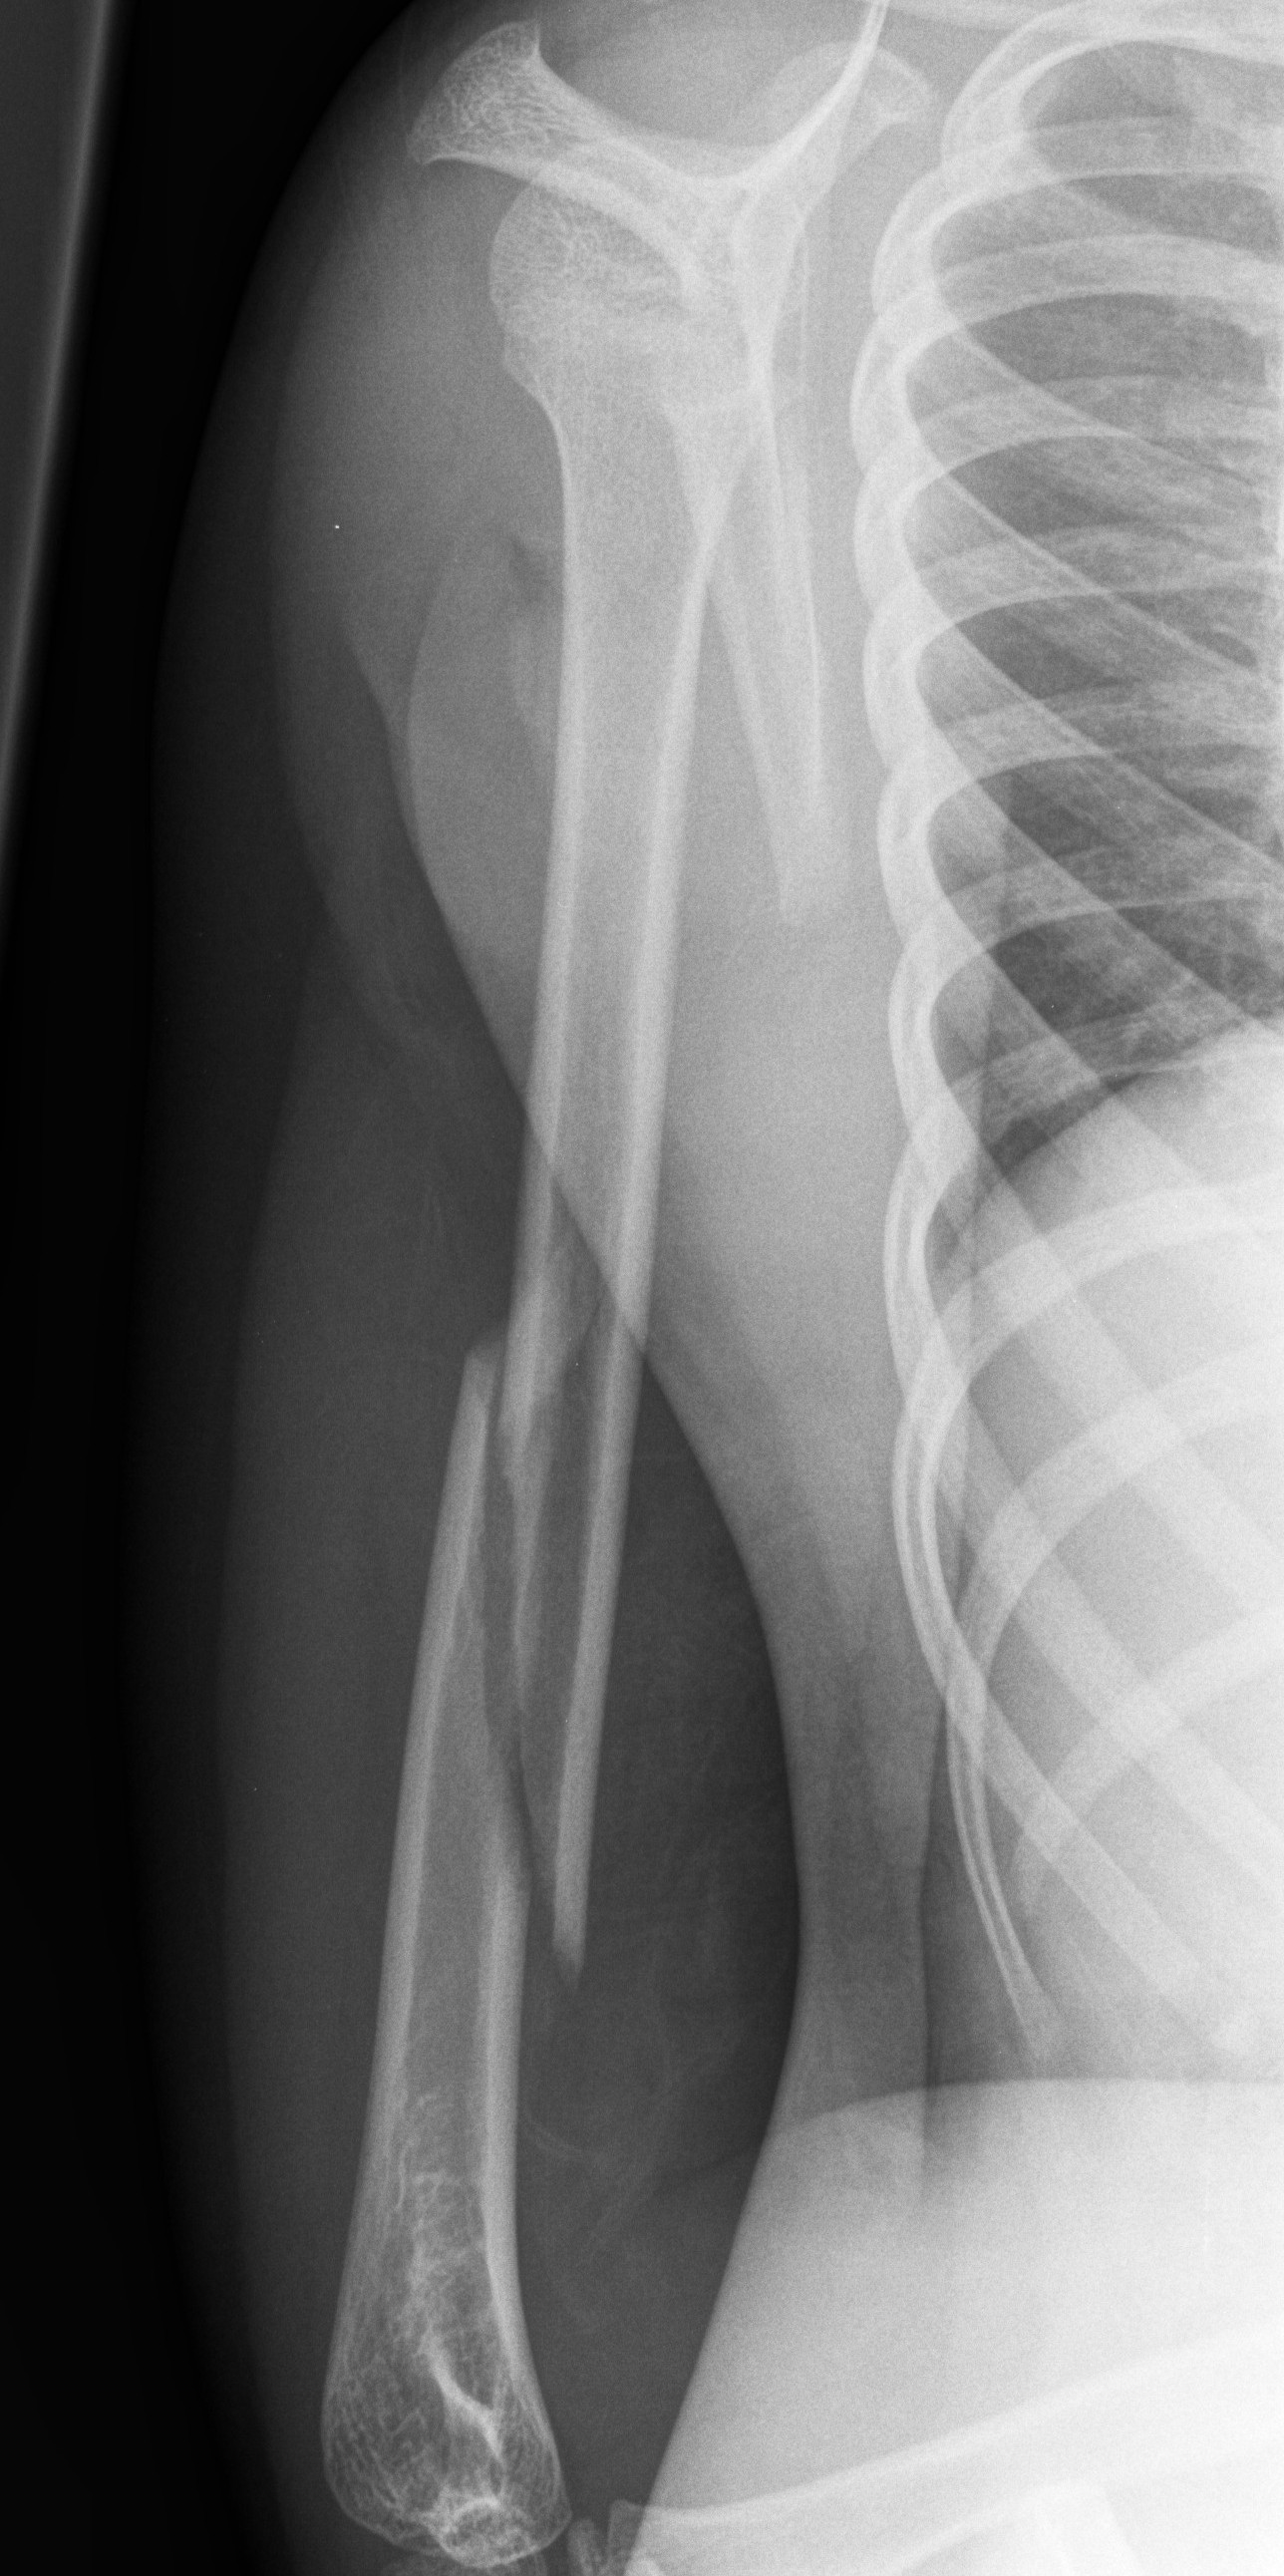

Above: Spiral fracture of shaft of humerus